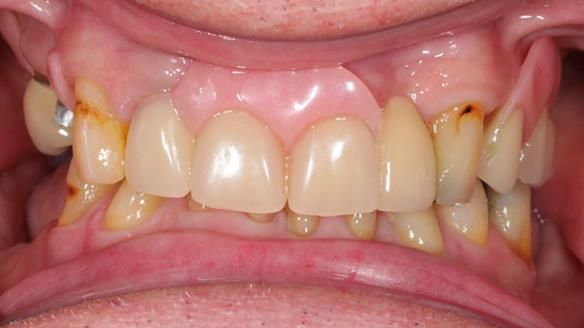

This edition features the case of Edgar, who sought help for a poorly fitting, acrylic-based partial denture that rocked, affected his speech, and caused discomfort. After considering various treatment options, including dental implants, Edgar opted for a metal-based removable partial denture, designed by myself with input from my technician, Rowan Garstang.

Despite significant improvements in comfort and aesthetics, Edgar expressed dissatisfaction with the denture's slight movement during certain jaw movements. This case underscores the importance of setting clear expectations, communicating limitations early, and ensuring both the patient and I are aligned on what can realistically be achieved. I must also be careful not to exaggerate the benefits of the treatment, to avoid creating false expectations.

Treatment Process: I provided the clinical work while Rowan Garstang delivered the technical aspects. The treatment required fifteen visits to fit and review Edgar.